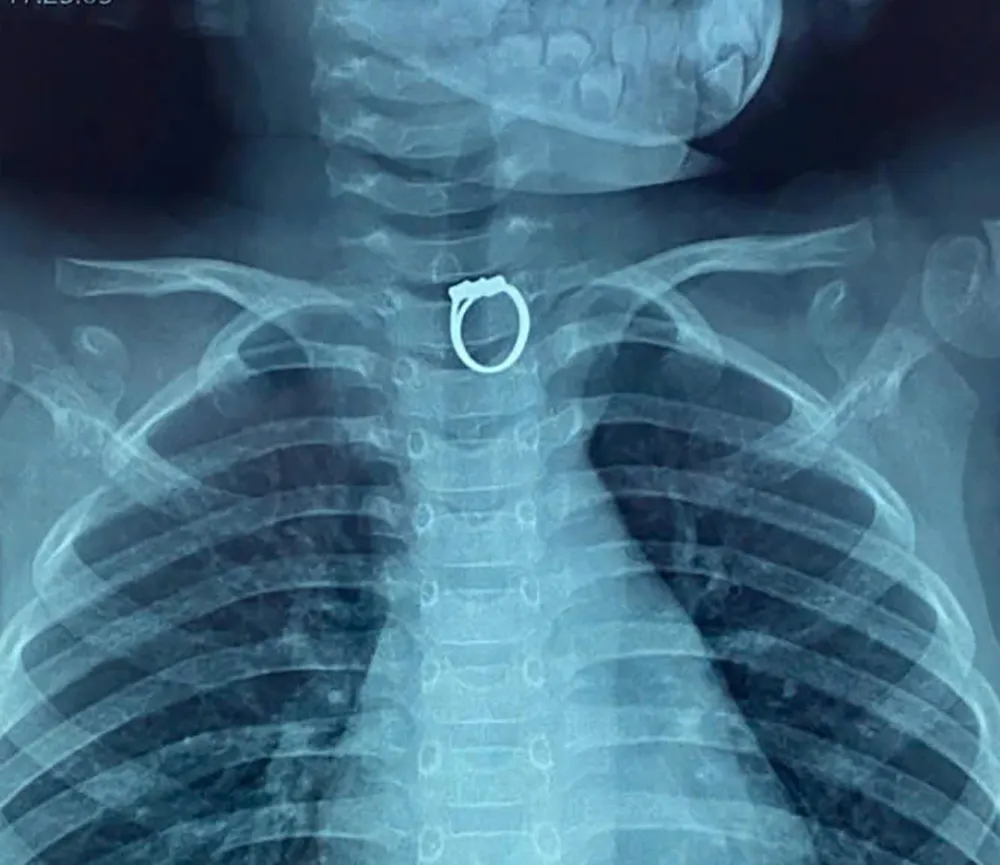

Phim chụp X-quang hiển thị chiếc nhẫn bị mắc kẹt trong thực quản bé gái

Qua chụp phim X-quang, các bác sĩ nhận thấy có dị vật là chiếc nhẫn trong thực quản bệnh nhi nên đã chuyển bệnh nhi lên phòng mổ và thực hiện ca nội soi. Kết quả, bác sĩ đã gắp ra chiếc nhẫn kim loại ra khỏi thực quản và sức khỏe của em đã ổn định.